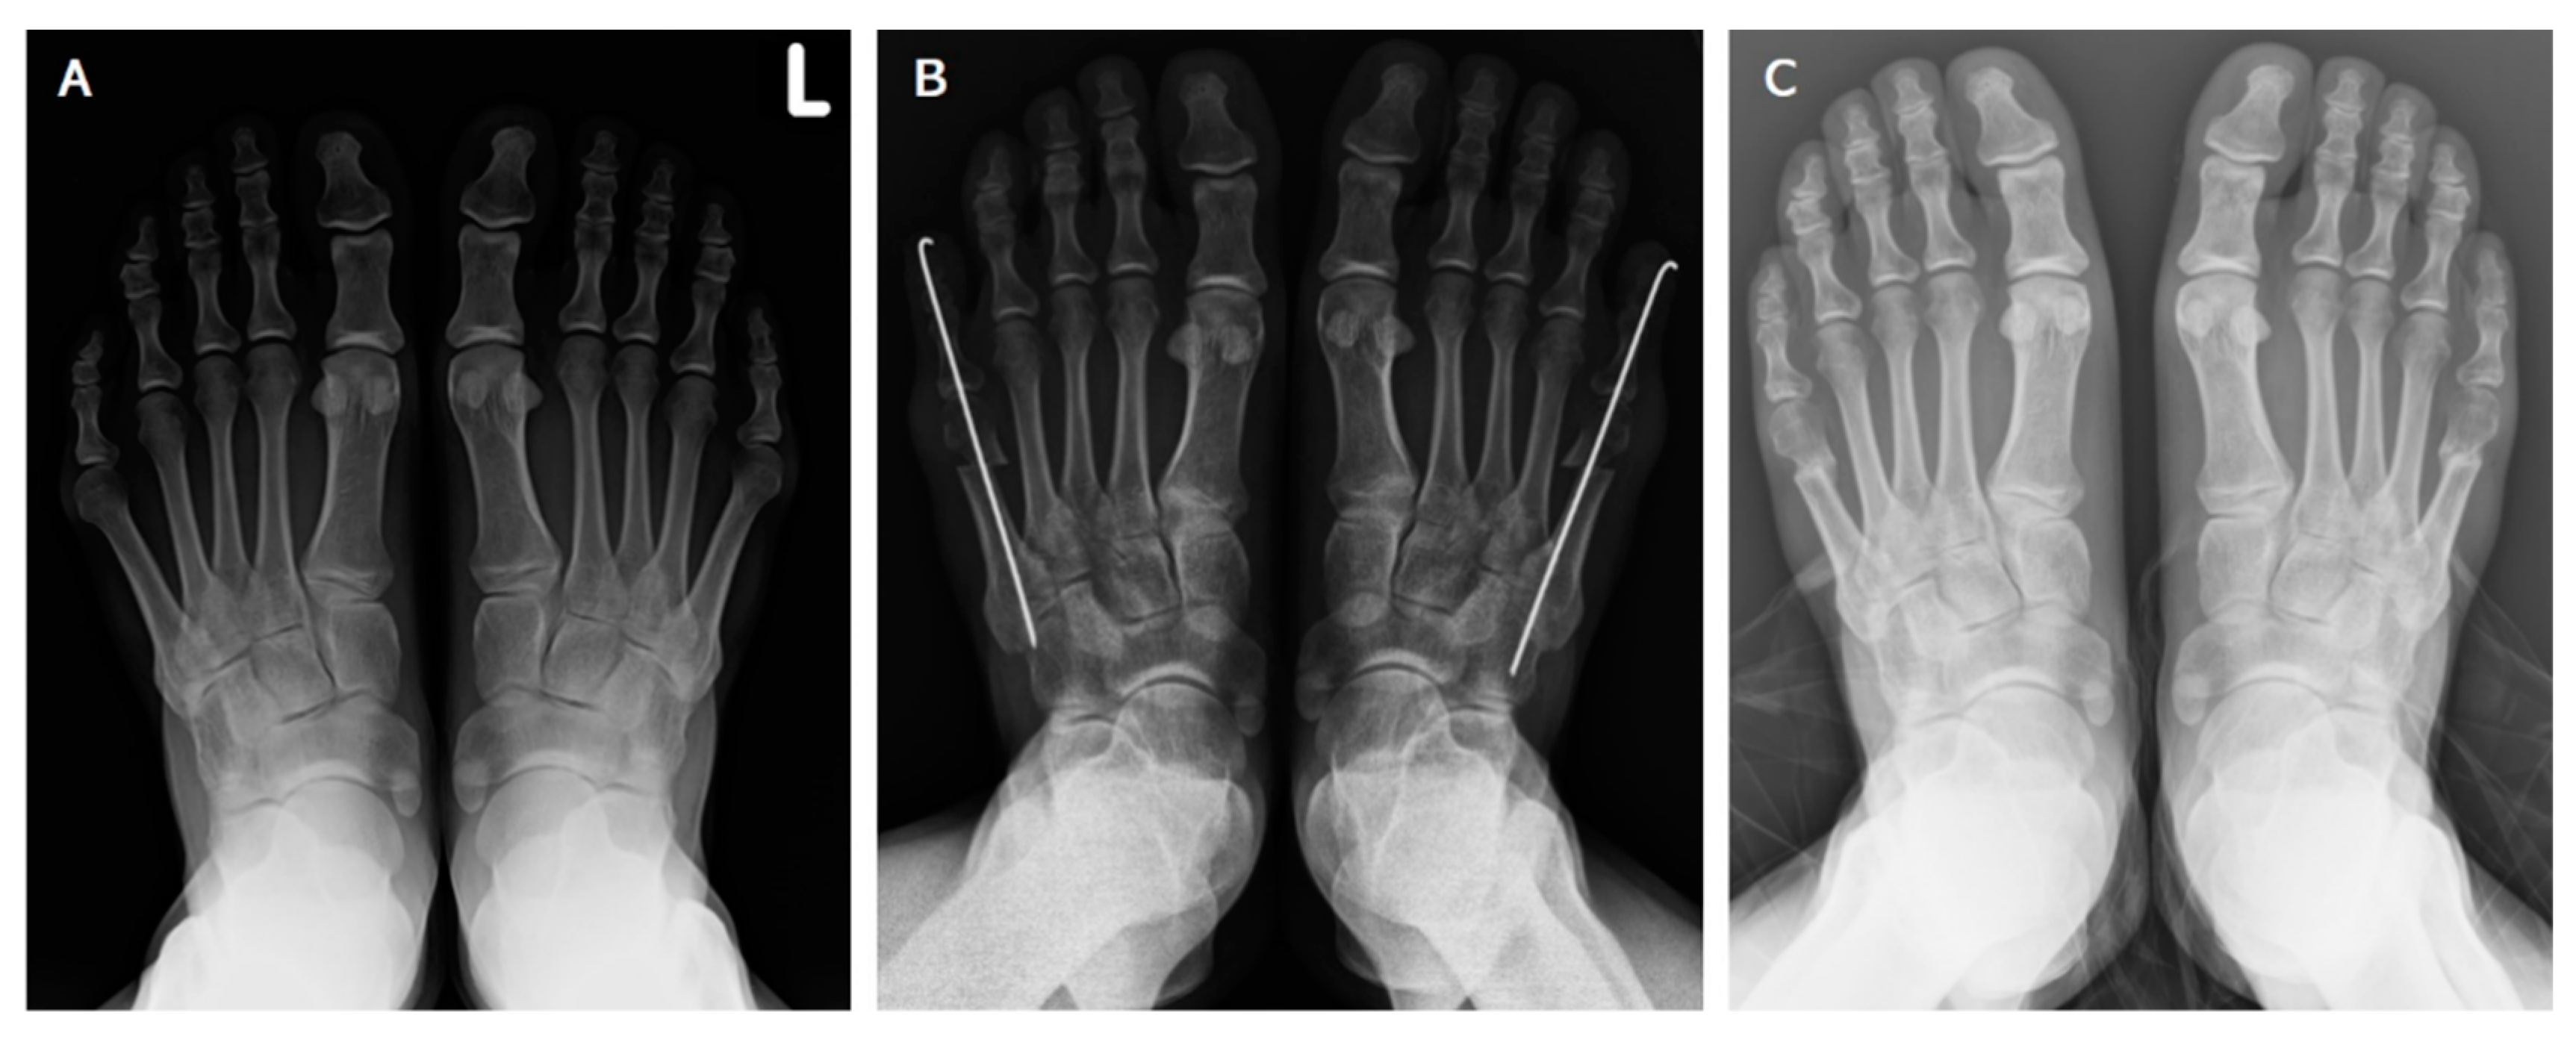

Symptomatic Bunionette Treated with Sliding Oblique Metatarsal Osteotomy—Case Series

Shen, Y.-T.; Huang, P.-J.; Chen, S.-J.; Chang, S.-M. Symptomatic Bunionette Treated with Sliding Oblique Metatarsal Osteotomy—Case Series. J. Clin. Med. 2022, 11, 3962. https://doi.org/10.3390/jcm11143962